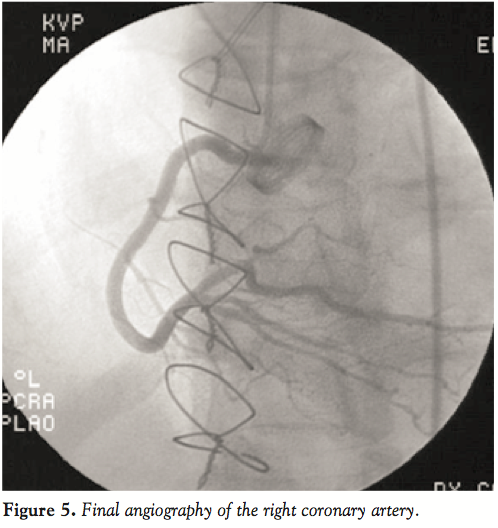

Diagnostic angiography of the left coronary system demonstrated complete occlusion of the LMCA (Figure 1). Fluoroscopy was also notable for a normal opening and closing bi-leaflet mechanical aortic valve. Given the scenario of cardiogenic shock, the decision was made to proceed with primary percutaneous coronary intervention. An intra-aortic balloon pump was placed for hemodynamic support. Intraveneous heparin and eptifibatide were administered with a peak activated clotting time of 293 seconds. A 300 cm BMW wire (Abbott Vascular) was advanced across the LMCA and positioned in the left anterior descending artery. After confirmation of intra-luminal location, a 2.0 x 15-mm Maverick balloon (Boston Scientific) was used to perform initial angioplasty of the LMCA with restoration of TIMI 2 flow, but with significant residual thrombus burden. Next, a 6 Fr ExPort catheter (Medtronic) was used to perform aspiration thrombectomy without retrieval of visible thrombus. A 7 Fr ExPort catheter was subsequently used to perform additional thrombectomy passes with improvement in flow (Figure 2) and removal of visible clot (Figure 3). However, given a persistently large clot burden in the LMCA, the decision was made to stent the vessel and compress the thrombus against the vessel wall. The left circumflex was a small non-dominant vessel, and a 2.75 x 23-mm Vision bare-metal stent (Abbott Vascular) was deployed in the LMCA into the LAD. The stent was ultimately post-dilated with a 3.5 x 15-mm NC Quantum balloon (Boston Scientific) to high pressure. Final angiography revealed TIMI 3 flow and no significant disease in the LAD (Figure 4). The right coronary artery was similarly free of significant angiographic disease (Figure 5).